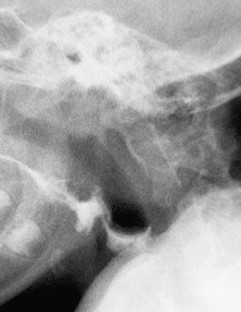

Fig. 1